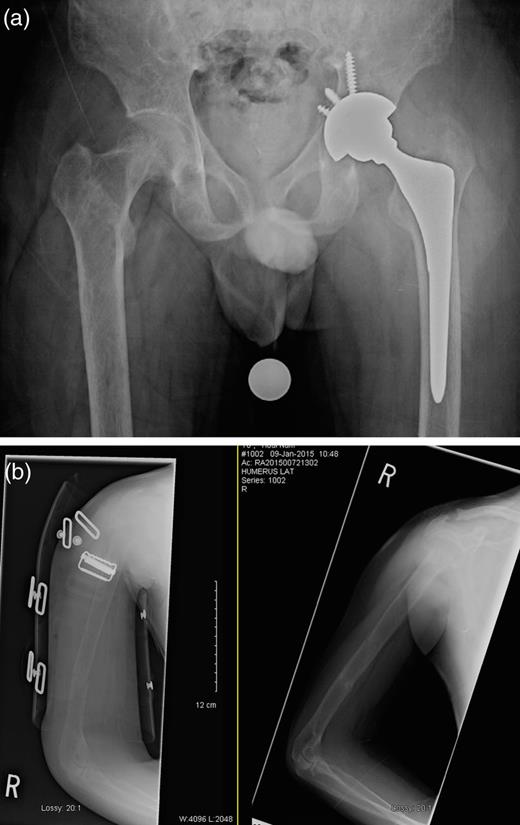

One day after sustaining this injury, the patient underwent an uncemented left total hip arthroplasty (THA) (Fig. 2), and acetabular fixation was supplemented with multiple screws, and he maintained touch-down weight bearing for 6 weeks postoperatively. His right humeral fracture was managed conservatively using a functional brace. A parathyroidectomy was performed 2 days later. The histopathology report confirmed the diagnosis of a parathyroid adenoma. Within 3 days postoperatively, the PTH level had decreased to 4.9 pmol/l, and the calcium level had returned to normal at 2.42 mmol/l. The calcium level continued to fall, and 2 weeks after the parathyroidectomy, it had reached 1.70 mmol/l. After a further 20 days, it started to normalize and then continued to remain stable, as shown in Fig. 3.